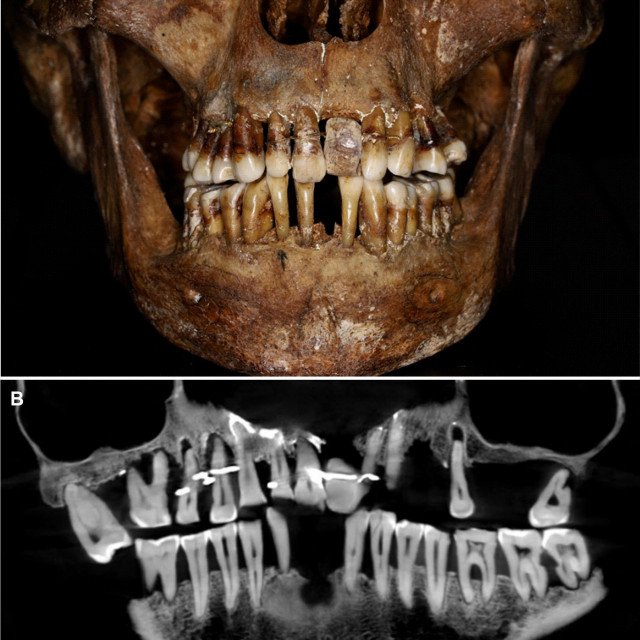

Lubanja francuske aristokratkinje Anne d‘Alegre

Balzamirana u olovnom lijesu, njezin kostur i zubi bili su izvanredno dobro očuvani.

Trideset pet godina kasnije, tim arheologa i stomatologa identificirao je da je d‘Alegre patila od parodontne bolesti zbog koje su joj se zubi klimali, prema studiji objavljenoj u Journal of Archaeological Science.

Skeniranje je pokazalo da je zlatna žica kori...